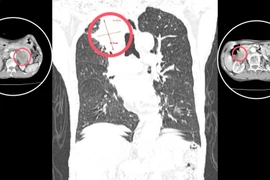

Một bệnh nhân trẻ tuổi có khối u tuyến giáp kích thước lớn, ác tính xâm lấn, di căn hạch cổ vừa được các bác sĩ Bệnh viện Bãi Cháy phẫu thuật thành công.